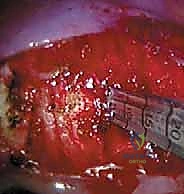

باستخدام جهاز الأشعة التلفزيونية (Fluoroscopy)، يقوم الدكتور هطيف بتحديد المستويات الفقرية الدقيقة التي سيتم العمل عليها. يتم رسم علامات على الجلد، ثم يتم عمل 3 إلى 4 شقوق صغيرة (بوابات) بين الأضلاع (Intercostal spaces).

* بوابة الكاميرا: لإدخال منظار الصدر عالي الدقة (Thoracosope).

* بوابات العمل: لإدخال الأدوات الجراحية الدقيقة (مثل المشرط التوافقي، الملاقط، وأدوات إزالة الأقراص).

الخطوة الثالثة: الدخول إلى تجويف الصدر وإفراغ الرئة

يتم إدخال الكاميرا، وتظهر الصورة بدقة 4K على الشاشات الكبيرة في غرفة العمليات. يتم إفراغ الرئة بالكامل (Lung deflation)، مما يكشف عن التشريح الداخلي للصدر: العمود الفقري، الأضلاع، الشريان الأورطي (أو الوريد الأجوف حسب الجانب)، والسلسلة العصبية الودية.